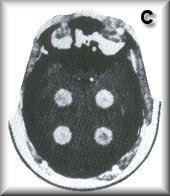

C部分:分級大小和放射性的圓柱形腫瘤建立高對比度和低對比度分辨率,并顯示部分光束平均效應。

RS-250 C部分